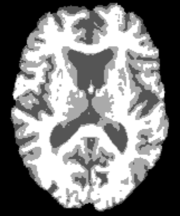

where 𝒙=(x,y,z)𝒙𝑥𝑦𝑧\boldsymbol{x}=(x,y,z) are the spatial coordinates and mg(𝒙)subscript𝑚𝑔𝒙m_{g}(\boldsymbol{x}), mw(𝒙)subscript𝑚𝑤𝒙m_{w}(\boldsymbol{x}) and mf(𝒙)subscript𝑚𝑓𝒙m_{f}(\boldsymbol{x}) denote the gray matter, white matter and CSF probability maps, respectively. These probability maps are obtained from binary segmentation labels for each tissue type of a healthy brain MRI scan.222In a pre-processing step, the binary labels are smoothed and re-scaled to probabilities. Our data d(𝒙)𝑑𝒙d(\boldsymbol{x}) is derived from actual patient MRI tumor segmentations.333We assign d(𝒙)=1𝑑𝒙1d(\boldsymbol{x})=1 to the voxels that have been identified as tumor. More complex scenarios are possible, for example see [5], which uses apparent diffusion coefficient (ADC) values to identify tumor tissue. Figure 1 shows an example of a healthy brain MRI scan (and its associated segmentation) and a patient brain MRI scan (and its associated tumor segmentation). As we discussed the healthy patient brain scan is rarely available in practice. There have been many approaches to address this, such as using a statistical average of many individual brains or image registration methods to approximate the healthy patient brain (see [56] for details). For the most part of this paper, we assume that the healthy patient brain segmentation is given. For our test on an actual clinical scan, we use an atlas-based segmentation in §4.7.

Refer to caption

(a)

(b)

(c)

(d)

Fig. 1: Imaging data which show an axial slice of (a) healthy T1 MRI scan, (b) segmentation of the healthy brain into white matter (white), gray matter (light gray), and cerebrospinal fluid-filled ventricles (dark gray), (c) patient T1 MRI scan diagnosed with glioblastoma, and (d) segmentation of the patient tumor sub-structures into enhancing tumor (white), necrotic tumor (dark gray), and edema (light gray). The patient scan and segmentation are taken from the 2018 Multimodal Brain Tumor Segmentation challenge training dataset [1], while the healthy brain scan and segmentation are obtained from the GLISTR dataset [20]. In our formulation, we assume the tumor core (enhancing and necrotic tumor) to be the tumor segmentation.